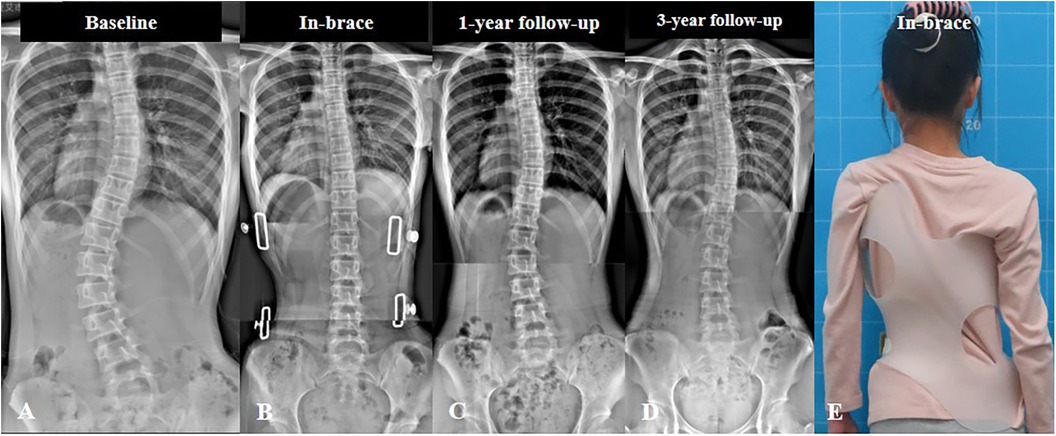

من أكثر الأخطاء شيوعًا أن يتوقف المريض أو الأهل عن زيارة الطبيب بعد بداية العلاج، خاصة إذا بدا أن الحالة تتحسن. لكن اعوجاج العمود الفقري يحتاج متابعة دقيقة، لأن زاوية الانحناء يمكن أن تتغير مع الوقت أو النمو عند الأطفال والمراهقين.

أظهرت الدراسات أن العلاج الطبيعي المنتظم، مع ارتداء الحزام في الوقت المناسب، يمكن أن يقلل الانحناء بشكل واضح دون الحاجة إلى جراحة في كثير من الحالات.

الاعوجاج حالة مستمرة ولهذا السب قد تحتاج تدخلًا في مراحل مختلفة من العمر. وبفضل وجود تقنيات التصنيف المعتمدة ، يمكن للأطباء تصميم خطة علاجية مخصصة تضمن تدخلاً جراحيًا عند الضرورة أو العلاج غير الجراحي قبل ذلك، لتفادي الاضطراب في الوظائف التنفسية أو أي أعراض متأخرة. فريقنا المحترف يضم نخبة من الأطباء والمتخصصين الذين يجمعون بين الخبرة والاحترافية لتقديم خطة علاجية غيرر جراحيه شاملة ومخصصة لحالتك، تضمن السيطرة على الانحناء ومنع زيادته.

خطط علاجية مخصصة: نوفر برامج علاجية مصممة خصيصًا لكل حالة لضمان أفضل النتائج دون الحاجة للجراحة.